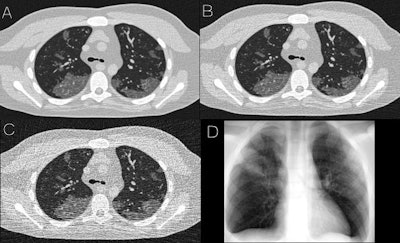

The simulated abnormalities -- ground-glass opacities and consolidation -- were visible and realistic in terms of shape and texture on both simulated CT and radiographic images, according to the authors. The team also found that contrast-to-noise ratios in the abnormal regions of the image were 1.6 for 5 mAs images, 3 for 25 mAs images, and 3.6 for 50 mAs images.

Simulated images of COVID-19 on 4D extended cardiac-torso phantom developed at Duke University, including simulated CT at 50 mAs (A), 25 mAs (B), and 5 mAs (C), as well as a simulated chest radiograph (D). Images and caption courtesy of the American Journal of Roentgenology.With virtual imaging trials, researchers could potentially investigate and optimize the role of radiography and CT in diagnosis and follow-up of COVID-19. These techniques enable the quality and performance of these imaging modalities to be comprehensively assessed and compared, according to Abadi et al. What's more, radiation dose and image quality could be quantitatively optimized.